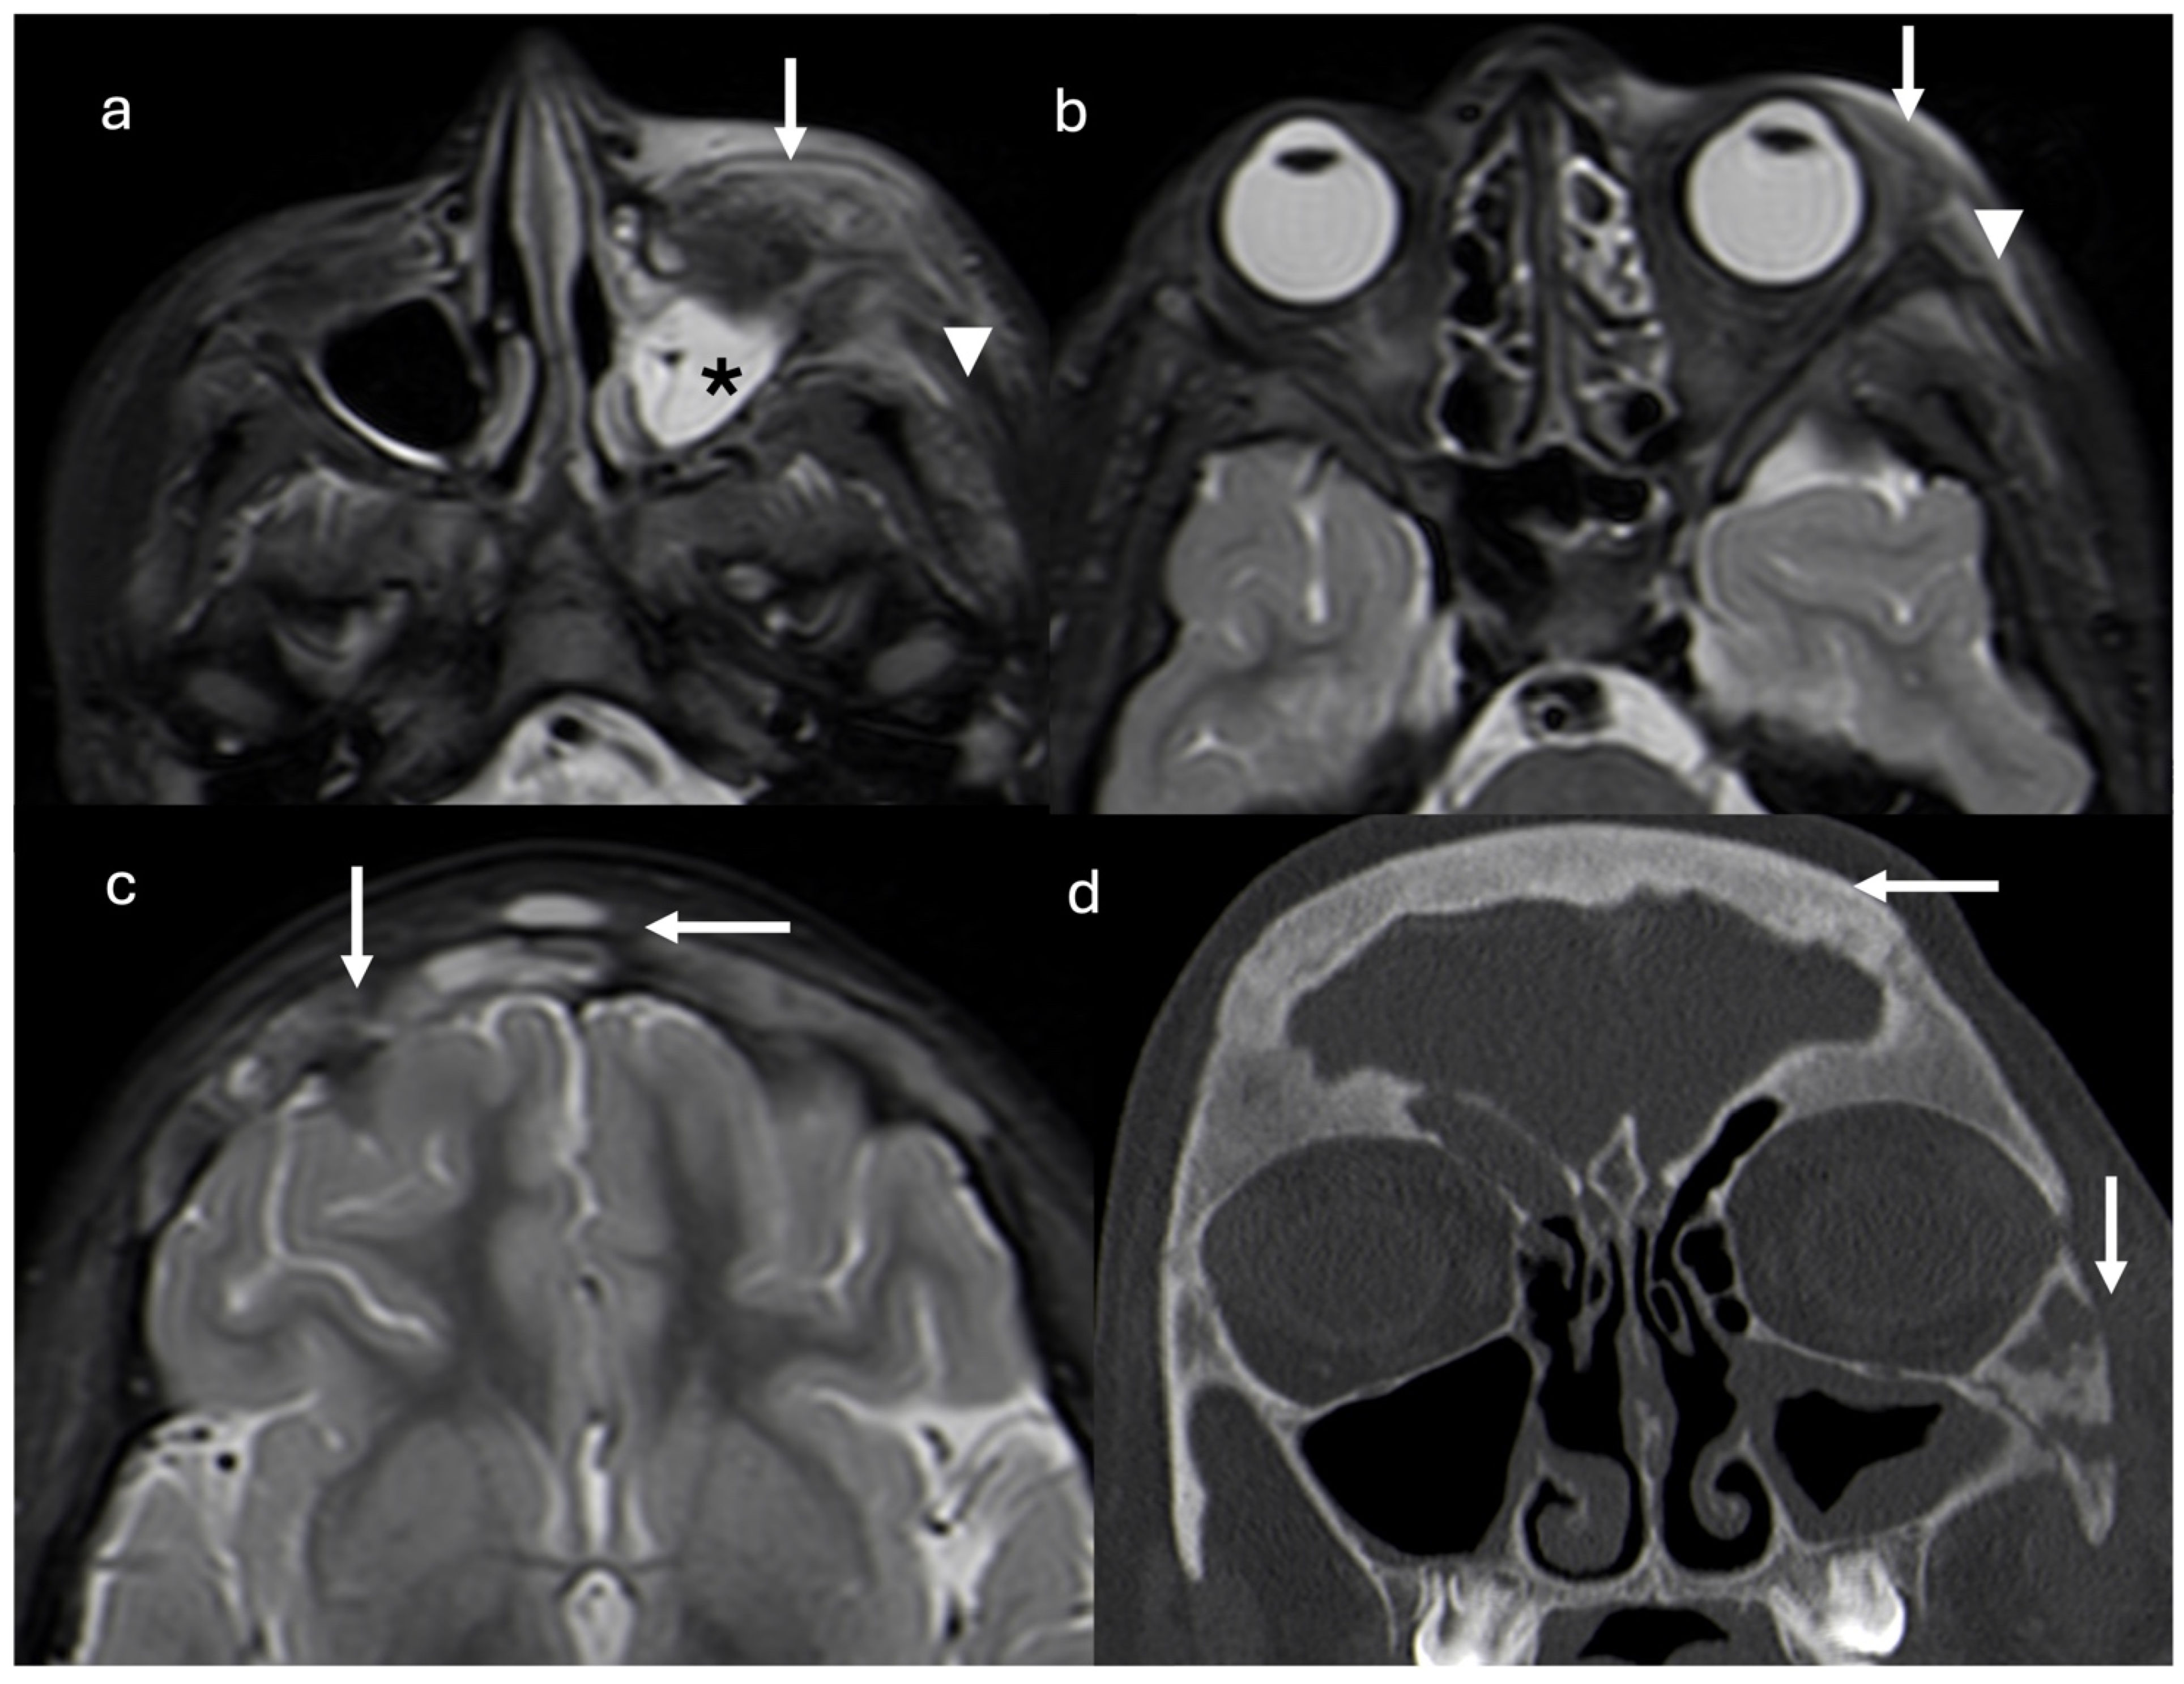

The follow-up CT scan showed lytic lesions at the frontal and zygomatic bones, and a magnetic resonance imaging (MRI) scan was required. One month after discontinuation of antibiotic therapy, MRI revealed a diffuse mucosal thickening of the left maxillary sinus, periorbital adipose tissue inflammation, pre-septal cellulitis, temporal and masseter muscle edema, and thickening and diffuse signal alterations of frontal bone with epicranic soft tissue involvement (Figure 2).

Axial short tau inversion recovery (STIR) magnetic resonance images show diffuse mucosal thickening of left maxillary sinus (asterisk), periorbital adipose tissue inflammation and pre-septal cellulitis (arrows), and temporal and masseter muscle edema (arrowheads) (a,b). Thickening and diffuse signal alterations of frontal bone with epicranic soft tissue involvement (arrows) are demonstrated (c). Coronal reconstruction CT scan (d) confirmed thickening on frontal and zygomatic bones with lytic areas. Right frontal and left maxillary sinus inflammation is present (arrows).